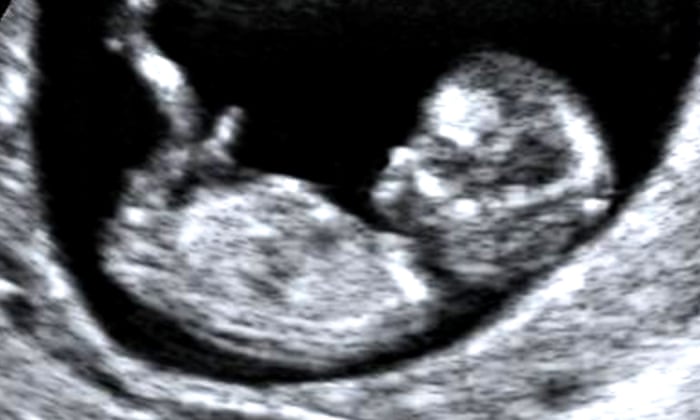

Gene therapy for unborn babies

The Guardian posted an article about doctor's using CRISPR to treat a rare brain disorder in unborn babies. The gene therapy they are using could mend the mutations in the womb that causes Angelman Syndrome. The treatment has never been tested before but it would involve the doctor's injecting a virus into the brain that infects the neurons and delivers molecules to correct the genetic faults. The disorder can be detected at 10 weeks and has been tested on a brain cell grown in a dish.  It is suggested that the procedure will be best performed in the second trimester. Normal brain development gene comes from UBE3A where the gene from the mother is "on" and from the father is silenced. During development the gene from the mother is missing or mutated, so the CRISPR technology turns the father's gene "on".